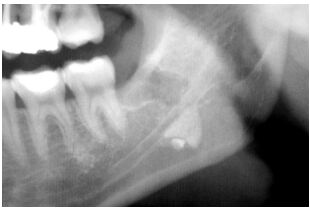

35.你為一位病患拔除下顎左側之阻生第三大臼齒,其環口 X 光片如下圖所示,當你以拔牙挺用力挖動牙齒時,該阻生齒突然失去蹤影,此時該齒最可能是位於何處?(A) 下顎骨髓內,下齒槽神經之上方 (B) 頦下間隙(submental space) (C) 顎下隙(submandibular space) (D) 頰間隙(buccal space)